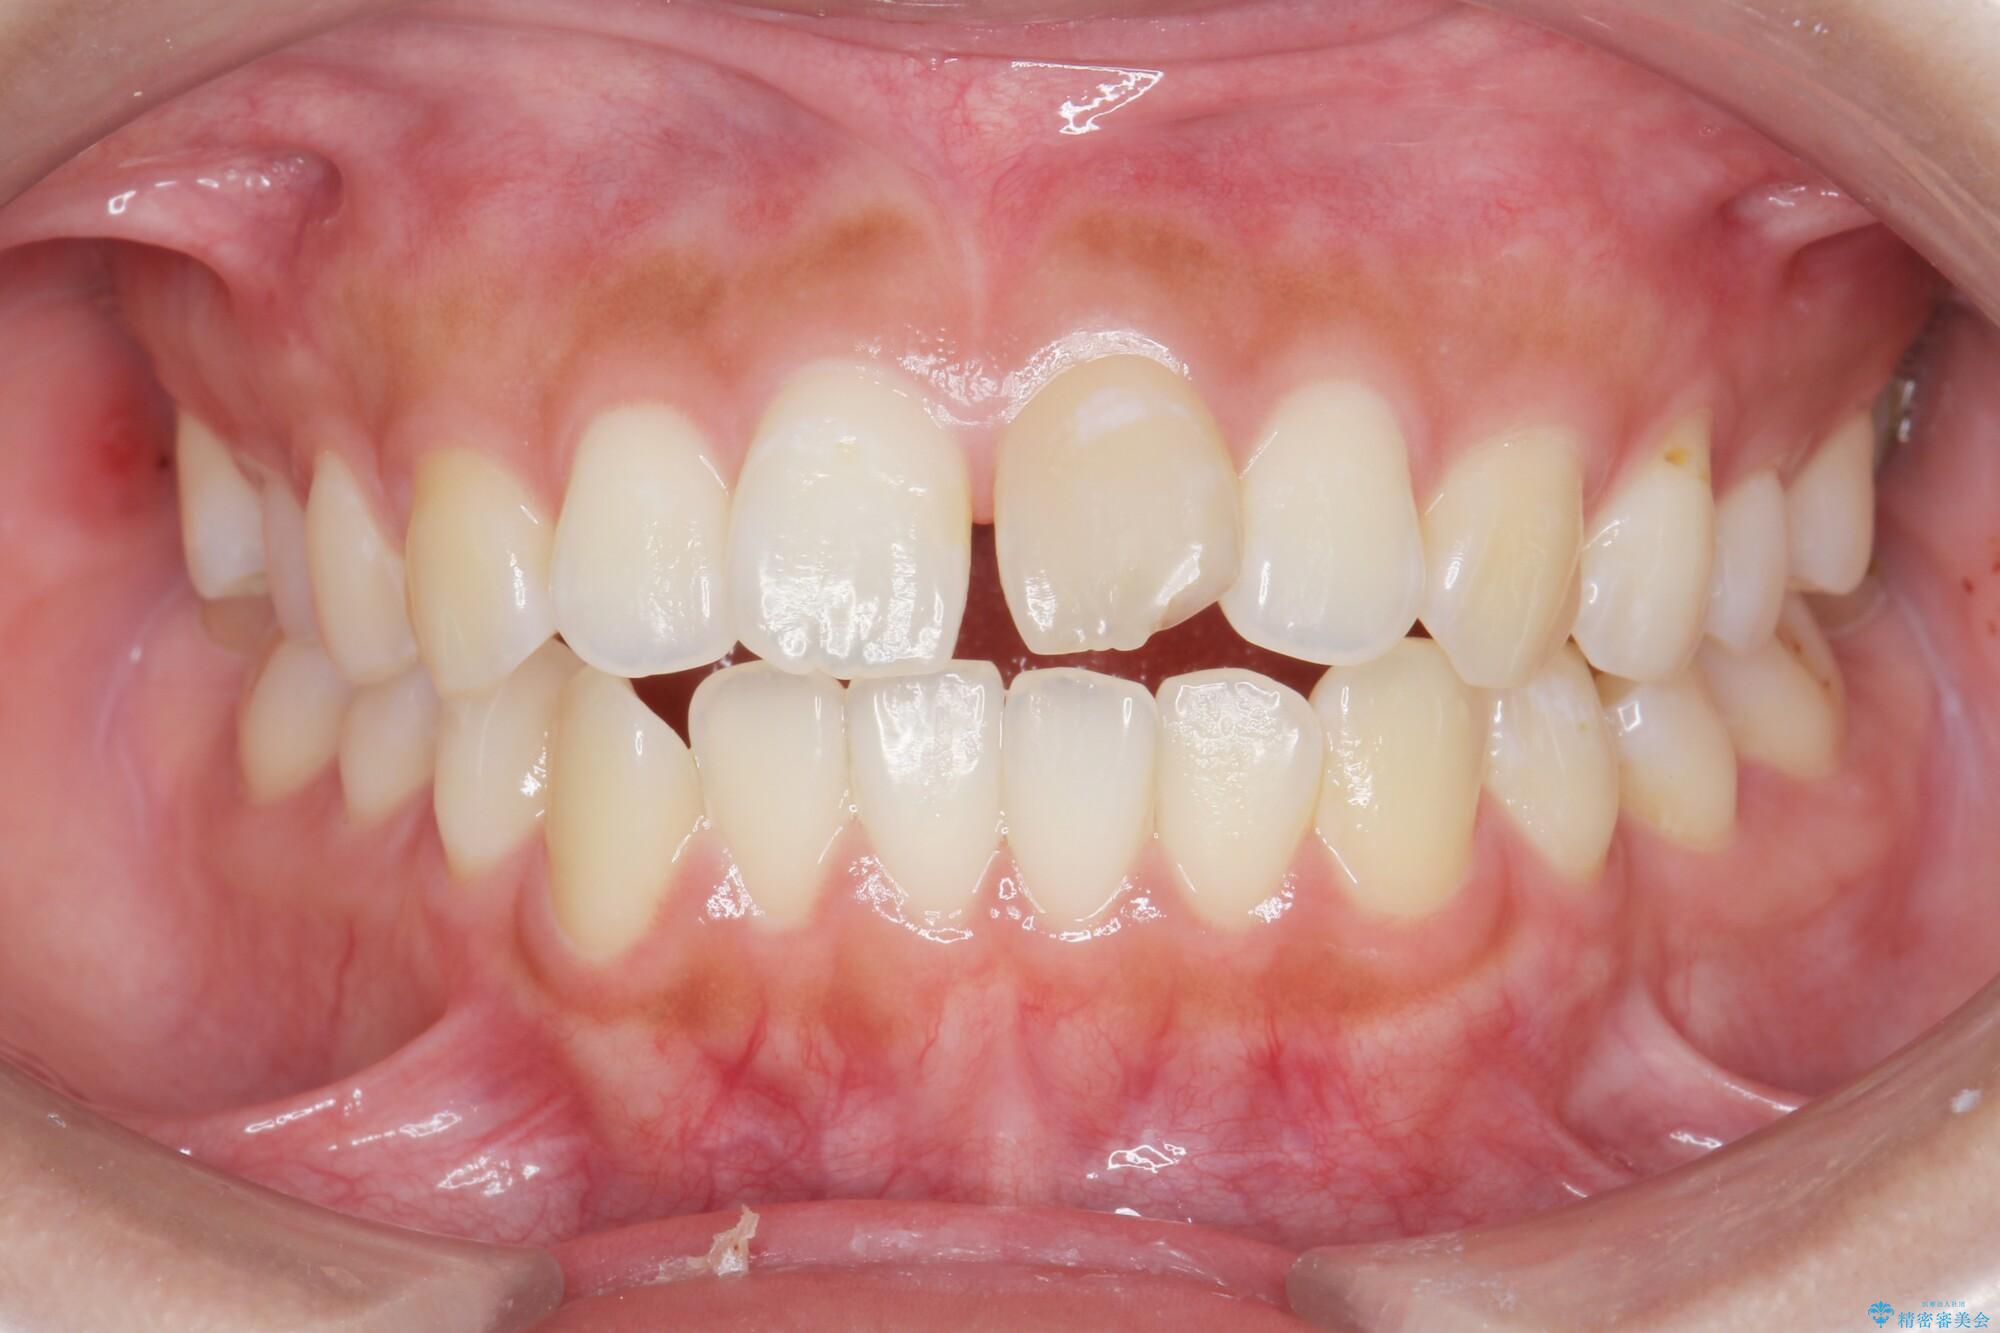

噛まない前歯と捻じれてしまった歯を改善したいと、矯正治療を希望された患者様です。

治療後について

1年で歯並び、嚙み合わせともにしっかりと改善されました。

患者様にも、非常に噛みやすくなったと喜んでいただくことができました。